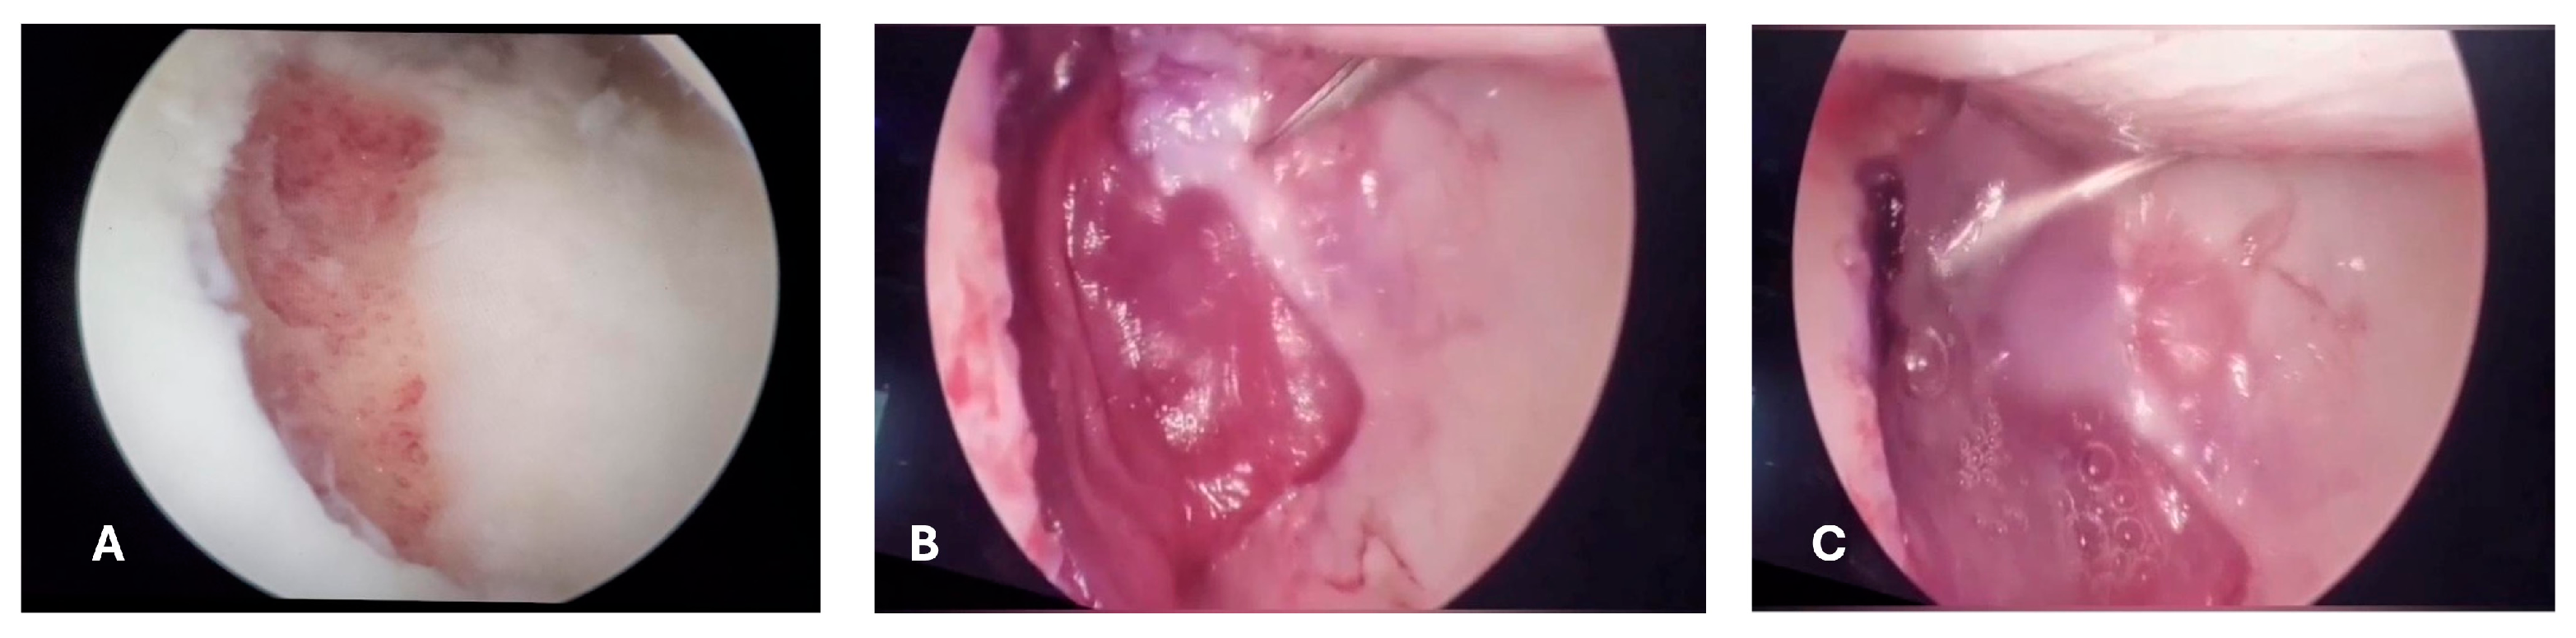

2. Case Report